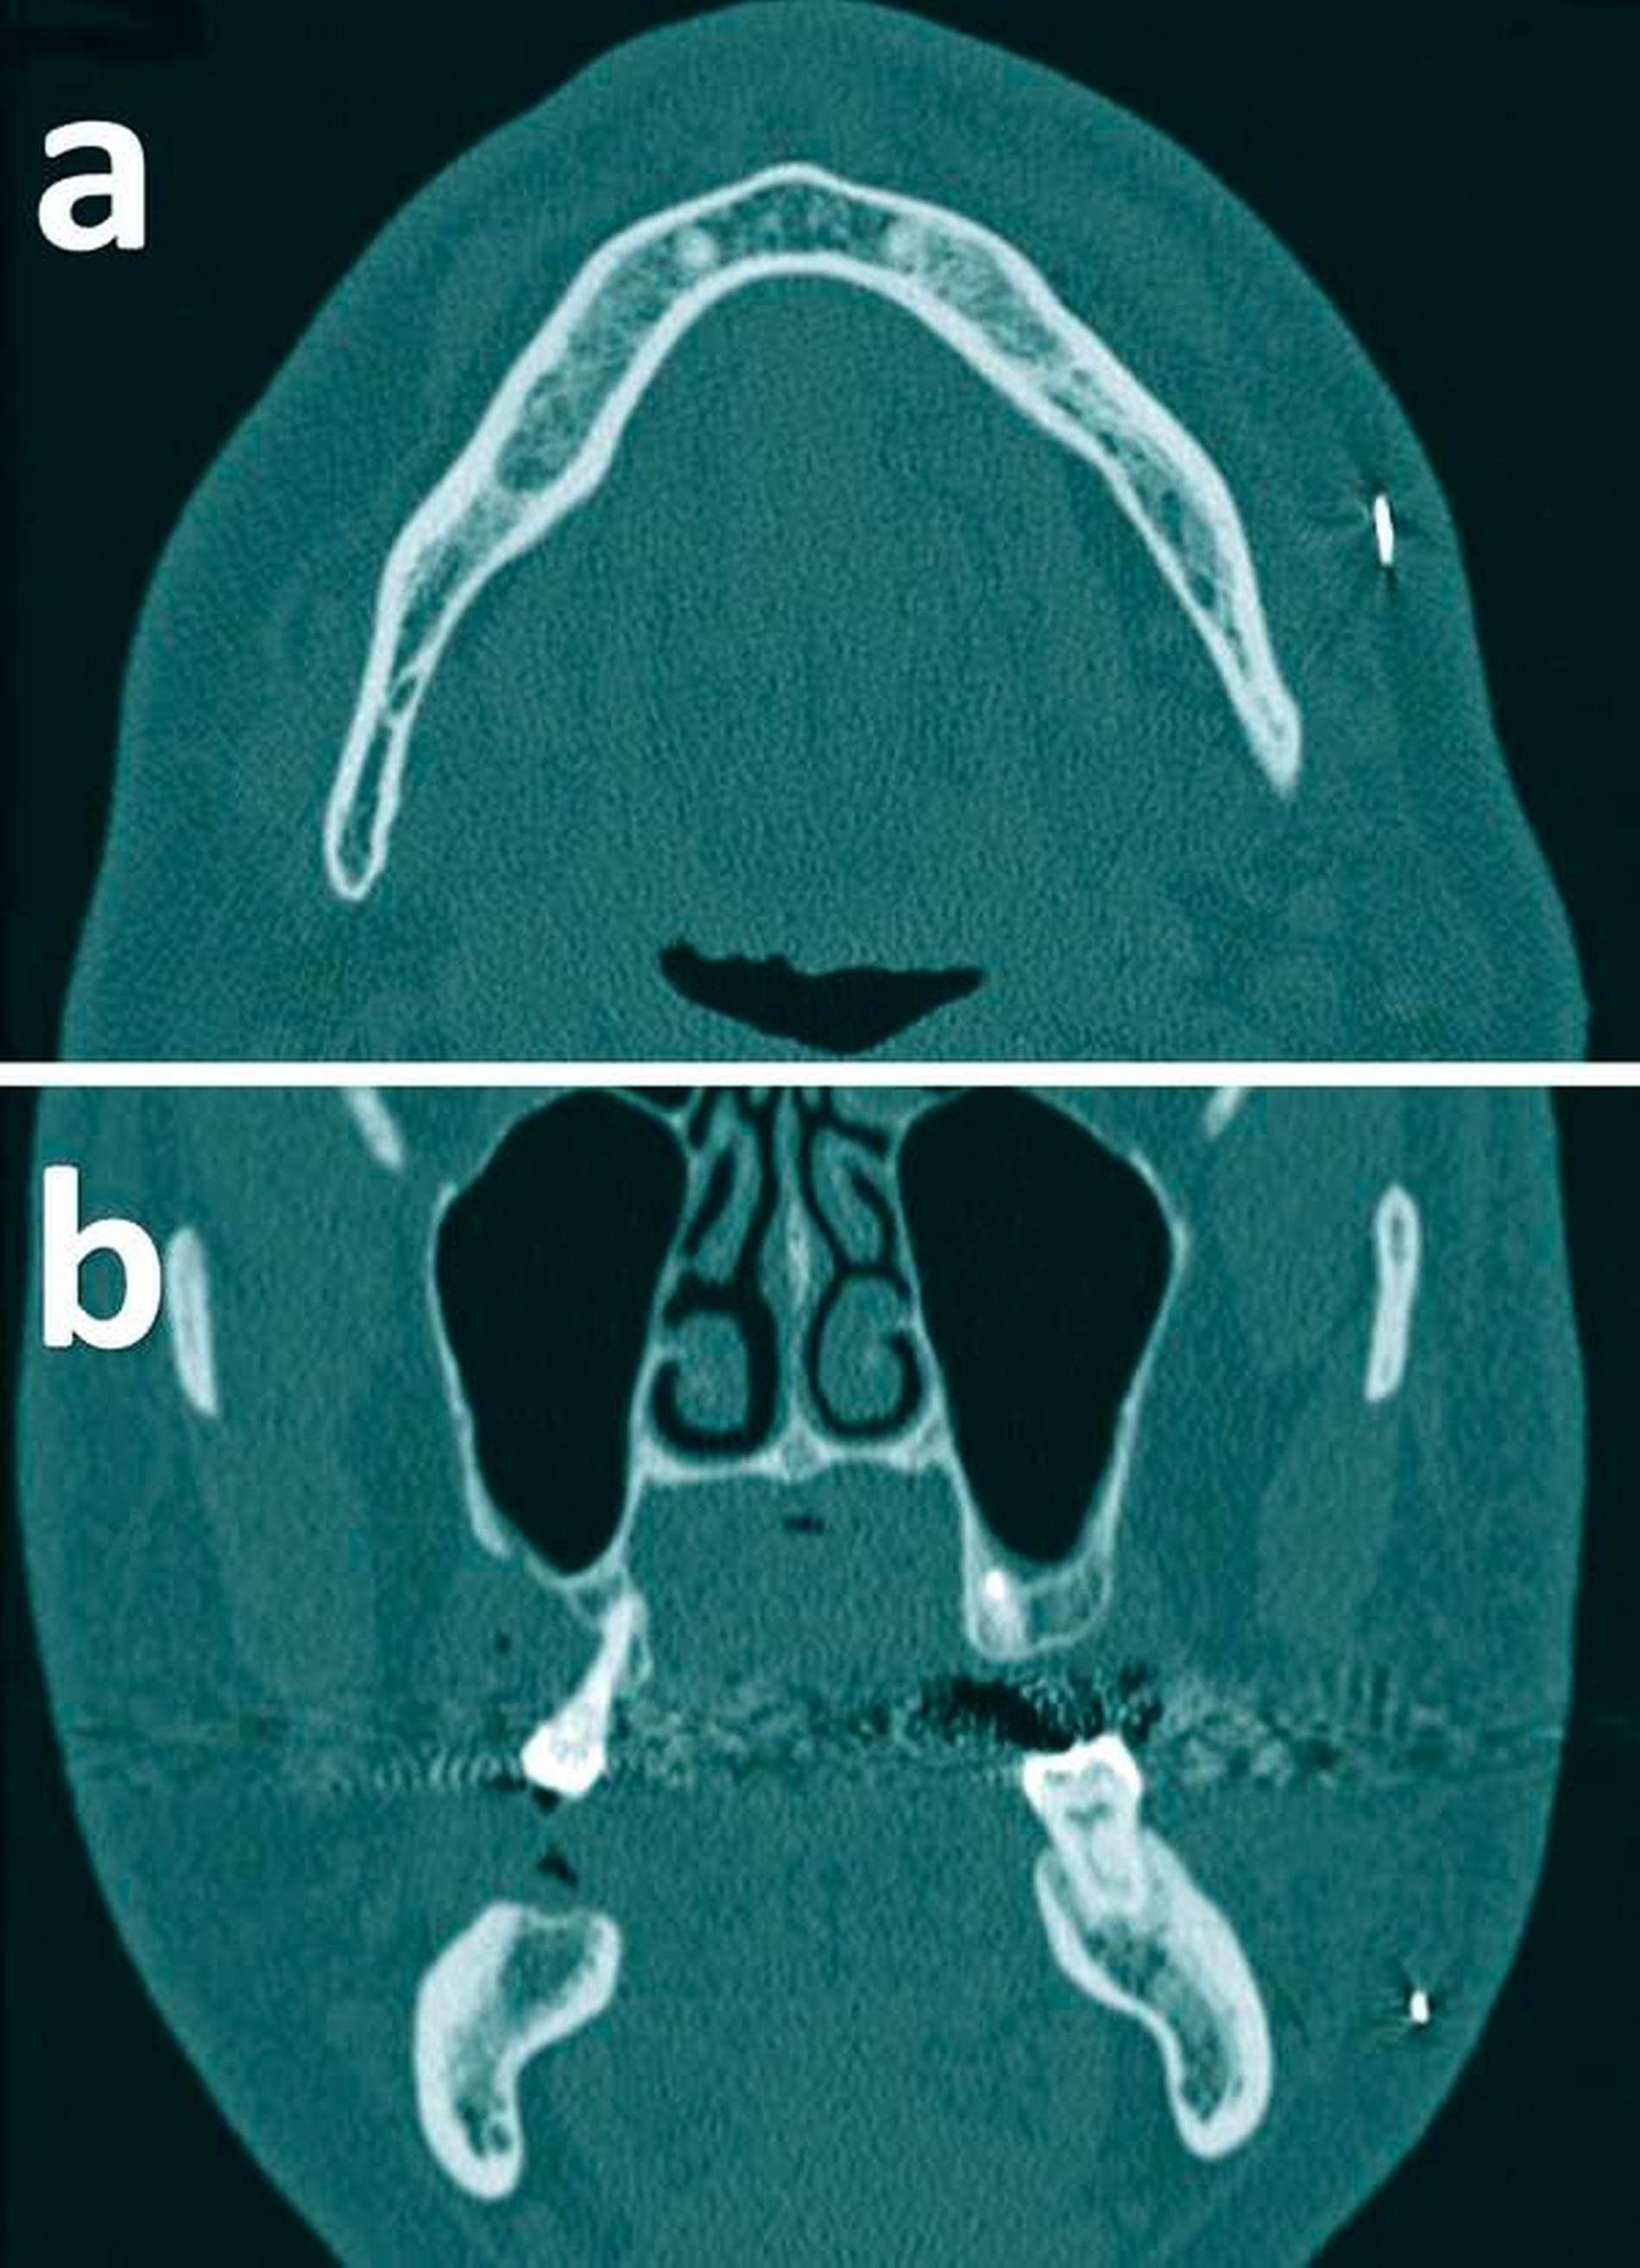

Mit dem Verdacht auf einen ins Weichgewebe der linken Wange eingedrungenen Fremdkörper wurde ein Unterkiefer-CT gefahren. Dieses zeigte einen röntgendichten, länglichen Fremdkörper im subkutanen Fettgewebe der linken Wange auf Höhe des Ansatzes des linken M. masseter (Abbildung 2).

Zum Frakturausschluss und zur Darstellung der exakten Position des Fremdkörpers bevorzugten wir schließlich als weitere bildgebende Diagnostik die Computertomografie (CT). Der Fremdkörper hätte in unserem Fall auch sonografisch diagnostiziert werden können, jedoch wäre hierbei das Auffinden einer Fraktur – insbesondere einer Infraktur – fraglich gewesen. Darüber hinaus kann nicht ferromagnetisches Fremdkörpermaterial auch mit der Magnetresonanztomografie (MRT) diagnostiziert werden [Cameron and Phillips, 2006; Vikram et al., 2012; Melo et al., 2017]. Wir haben uns hier nicht nur wegen des erheblich größeren Aufwands, sondern auch aufgrund des unbekannten Fremdkörpermaterials strikt gegen letztgenannte Bildgebung entschieden. Bei einer MRT hätte es bei dem Patienten möglicherweise aufgrund der ferromagnetischen Fremdkörpereigenschaften zu unvorhergesehenen Komplikationen kommen können.